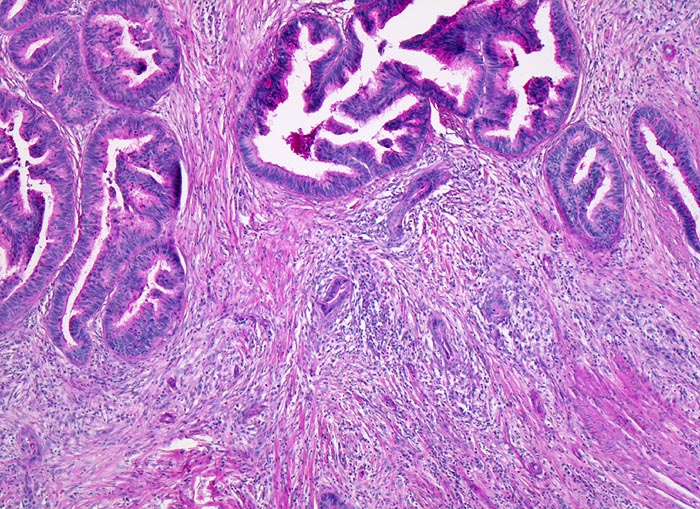

mässig differenziertes Adenokarzinom

Kolon Sigma

Karzinomdrüsen mit komplexer Architektur in der Submukosa. Dichtes desmoplastisches Stroma und Entzündungszellen umgeben die Tumordrüsen.

Der Patient wird wegen neu aufgetretener Obstipation abgeklärt. Koloskopisch kommt im Kolon sigmoideum ein polypoider, das Lumen stenosierender stark karzinomverdächtiger Herd zur Darstellung. Die Biopsie zeigt atypische Drüsen mit desmoplastischer Stromareaktion stark verdächtig auf ein invasives Karzinom. Da an der oberflächlichen Biopsie ein invasives Wachstum nicht nachgewiesen werden kann, lässt sich das Karzinom jedoch nicht beweisen. Es wird eine Sigmaresektion durchgeführt.